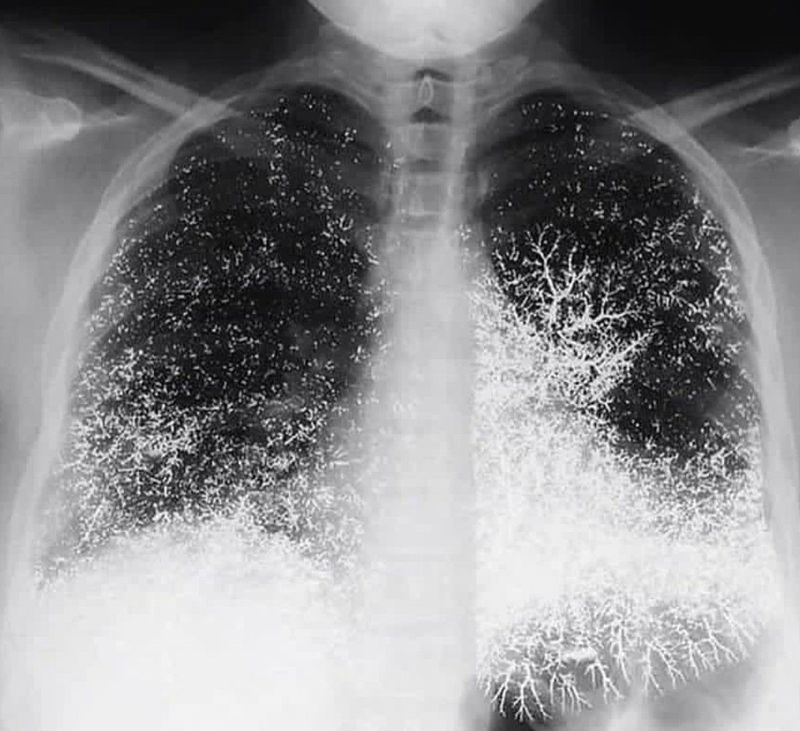

What's your dx? ?

Silicon or mercury poising

Hg poisoning

Mercury embolism

IV mercury poisoning

Mercury poisioning

silicosis

hydrargyria